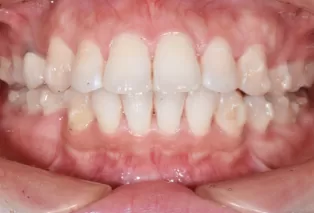

Intraoral photos after treatment